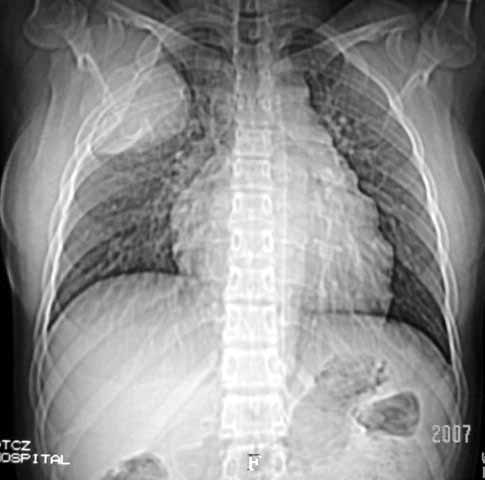

以下是引用dyqct在2007-5-26 12:01:00的发言:[br]右第二肋腋侧呈明显膨胀性、分叶状改变,内无明显间隔,ct值49hu,病变大小约67x57mm,周围硬化缘无断裂,内缘见多数骨嵴,肿块与正常骨间界限清楚。无移行带。周围软组织无浸蚀,胸膜腔无积液。[br]考虑:1、右第二肋动脉瘤样骨囊肿可能性大;[br] 2、需同骨巨细胞瘤、浆细胞瘤、骨纤鉴别。